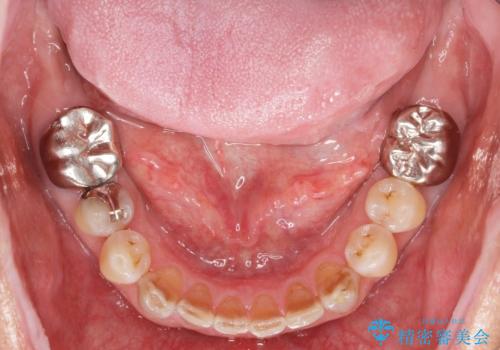

- 他院で上顎は全て抜歯し、入れ歯にする必要があると言われ相談に来院されました。

検査の結果、重度の歯周病であることから保存が難しい歯は抜歯を行いインプラントを、残すことが可能な歯には再生治療を含めた歯周病治療を行いより多くの歯を残す歯周病治療を計画します。

上顎は、残っている前歯も揺れがあり残すためにはクラウンでつなぐ歯周補綴が必要な状態です。

また咬合負担に不安のある前歯を助けるためにも、臼歯部にインプラント補綴を行いしっかりとかめる状態とすることも大切です。